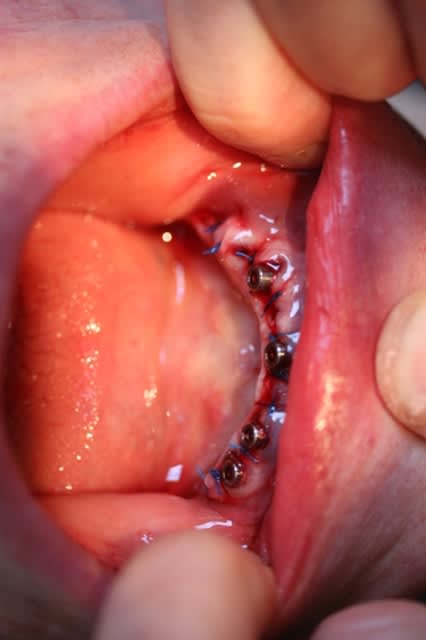

les photos

photo 10 ; on voit les parties femelles qui sont posée sur les piliers . on décharge le complet au niveau des piliers, un peu de résine, remettre en bouche, faire mordre, quelques mouvements et le tour est joué!

les parties femelles restent dans le complet (qui peut être le complet d'usage du patient) et la stabilisation est immédiate.